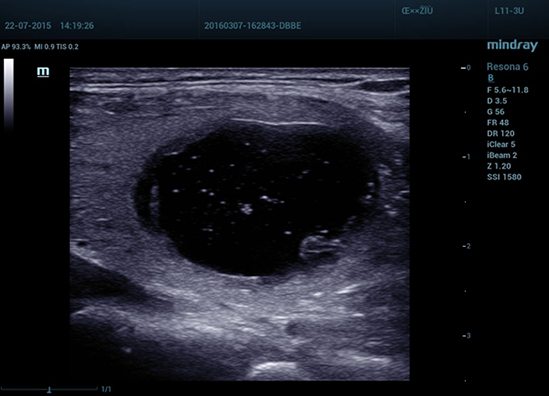

Улучшенная обработка канальных данных

Технология ZST+ обеспечивает улучшенную обработку канальных данных, что позволяет существенно повысить четкость визуализации. Многократная ретроспективная обработка канальных данных позволяет эффективно использовать акустическую информацию для улучшения качества изображений.

· Область HD: более четкое изображение в пределах области интереса.

· Когерентный пространственный синтез: дальнейшее улучшение качества изображения при пространственном объединении.